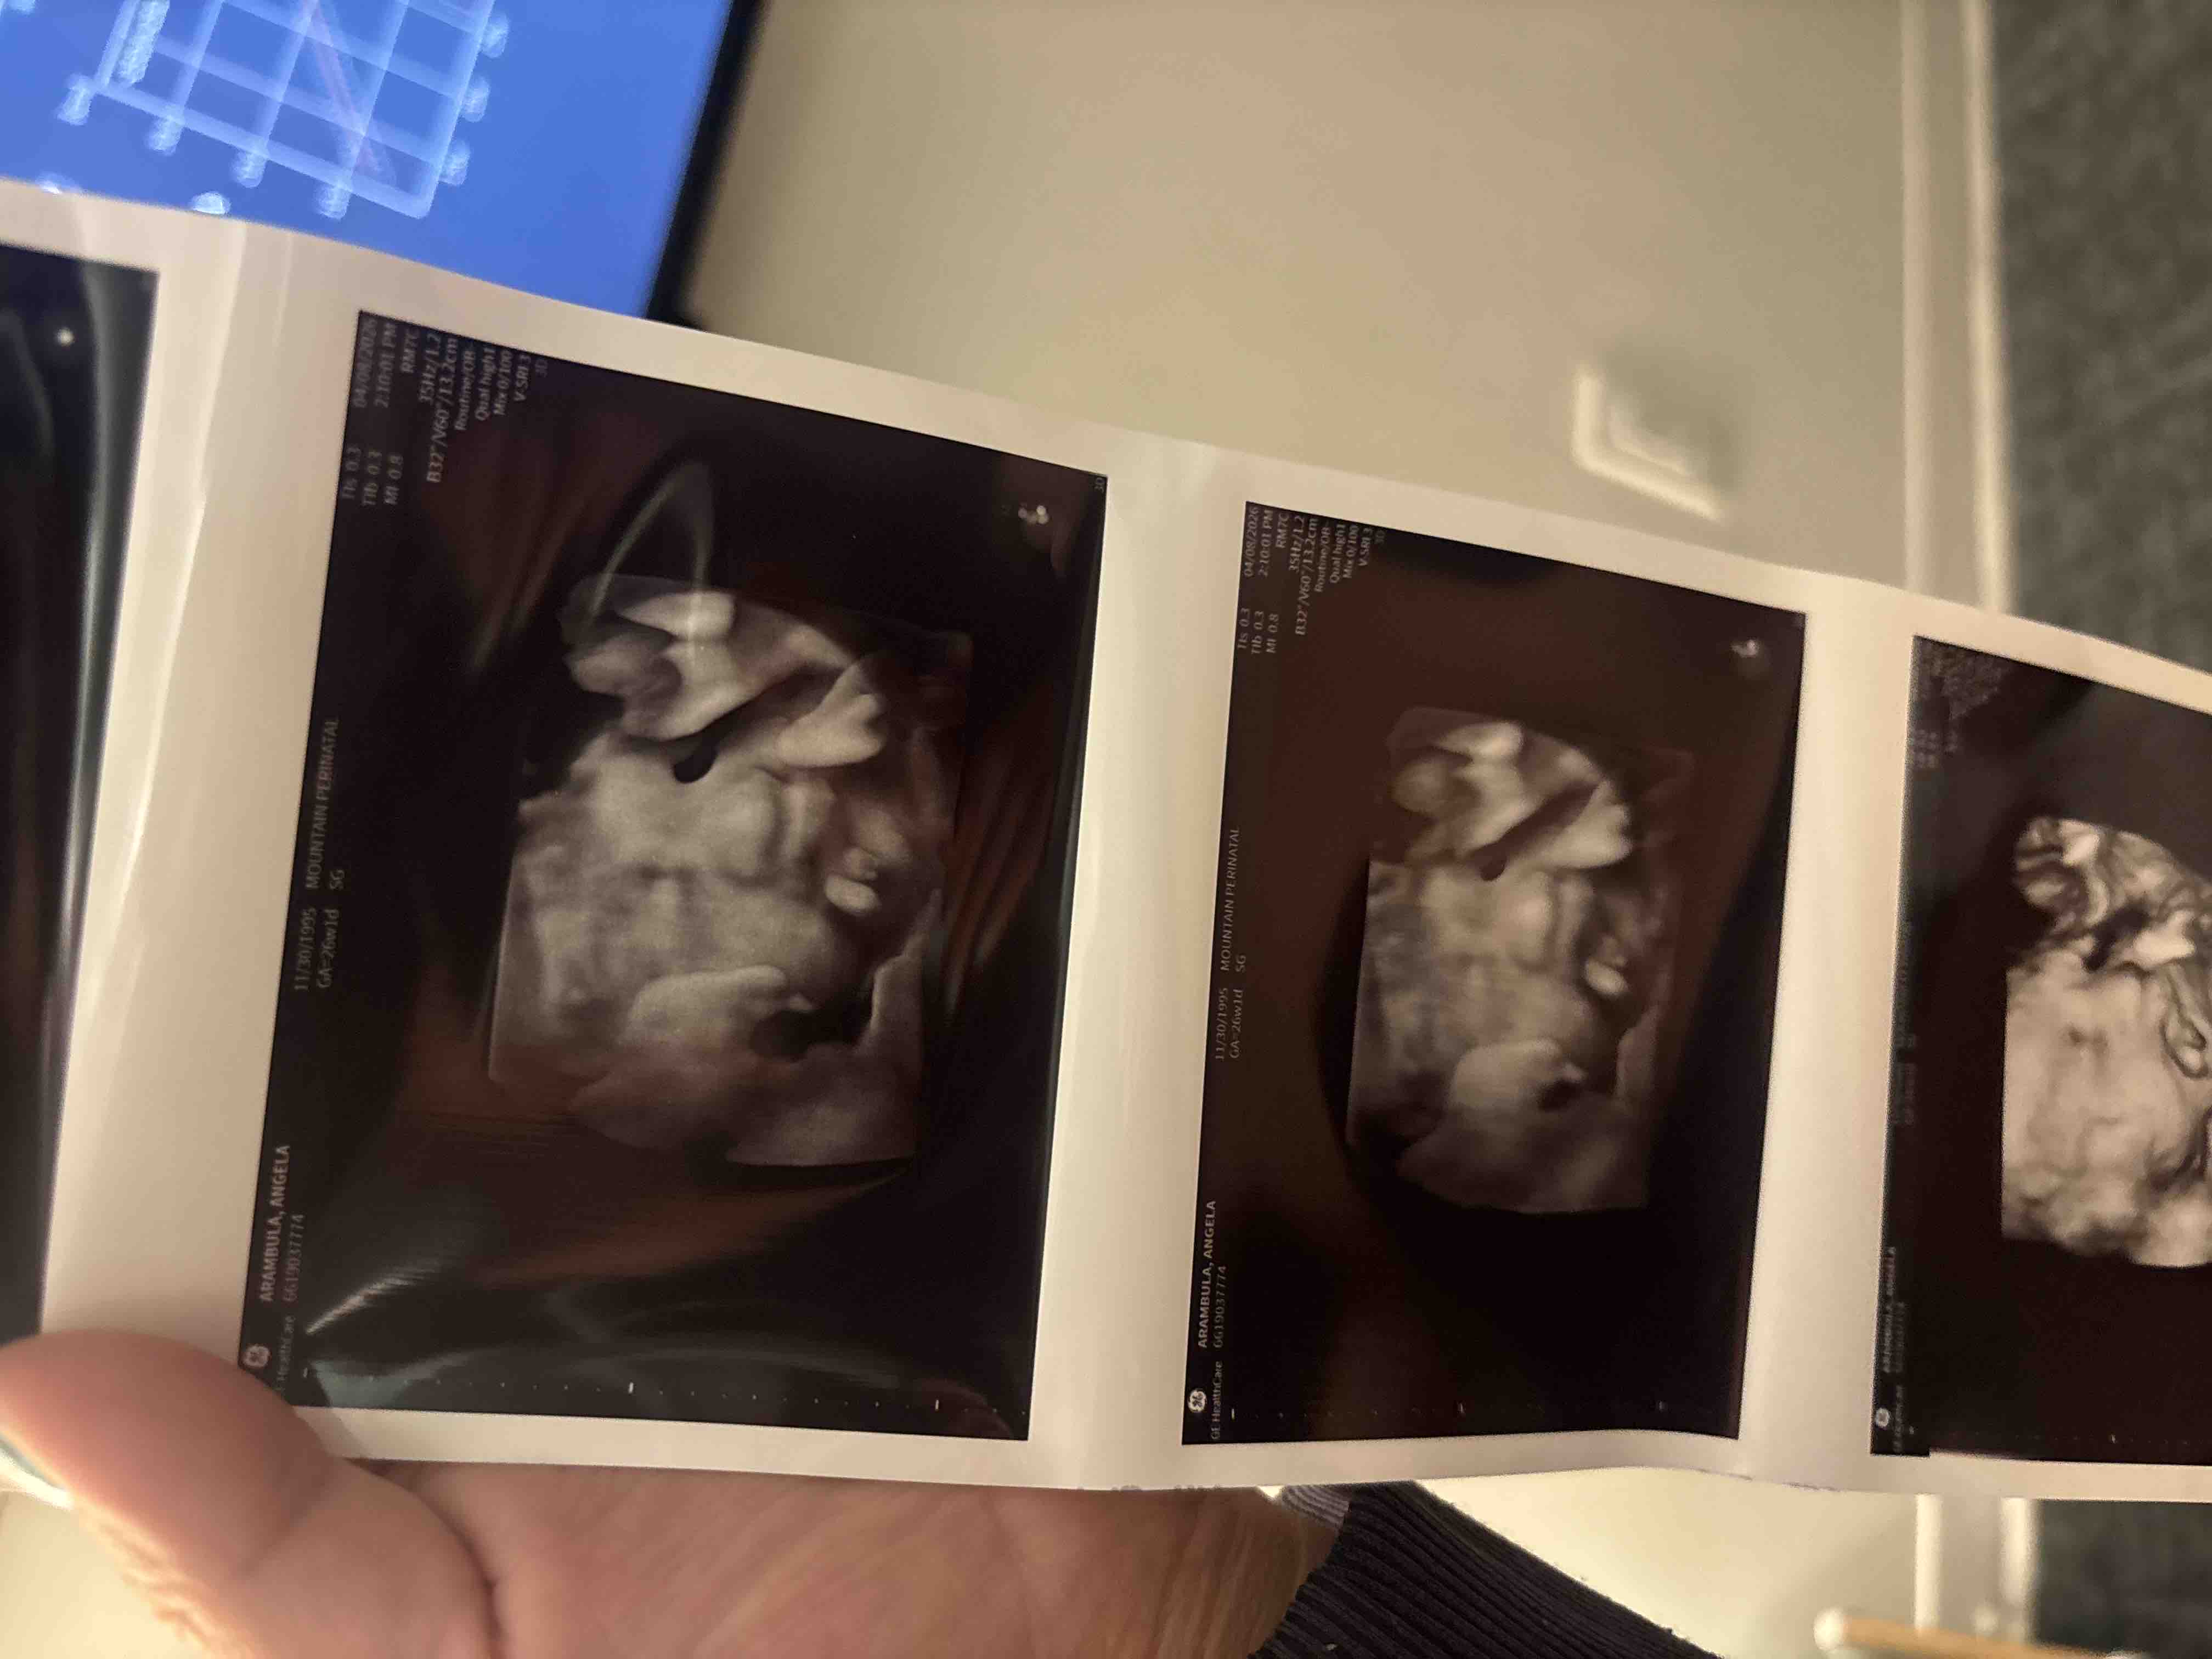

Hello friends and family. Our son has a rare lung lesion called CPAM, which could potentially affect his airway. At 23 weeks gestation, I had to switch OB’s and care team from Bakersfield to Los Angeles for better treatment options. Consequently, I will need to stay in Los Angeles for some time before and after birth, especially if he requires surgery. In light of these circumstances, we kindly request any assistance you can provide to cover the costs associated with our stay, including food, gas, and other expenses. Your support means the world to us as we care for our precious baby boy. We truly appreciate your generosity and compassion. Thank you from the bottom of our hearts. God bless